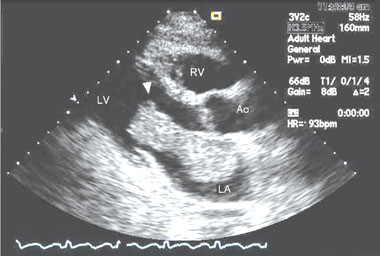

- 1. Rogers EW, Weyman AE, Noble RJ, Bruins SC. Left atrial myxoma infected with Histoplasma capsulatum. Am J Med 1978; 64: 683-690.